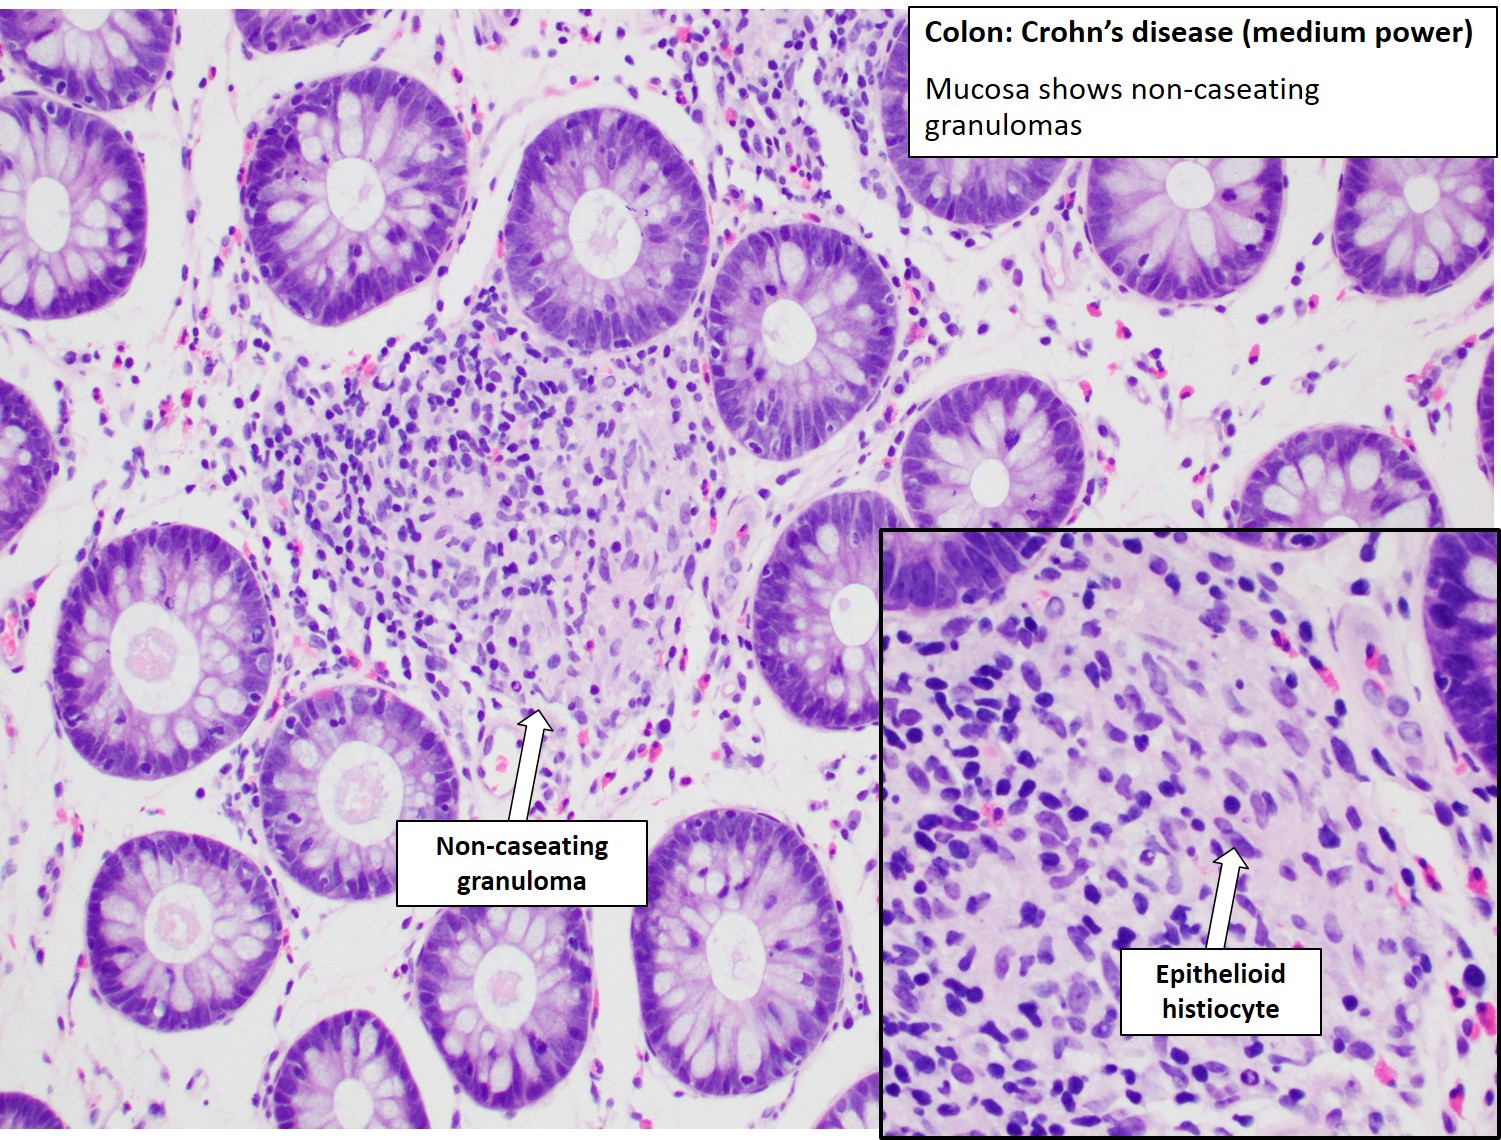

Фотографии медицинских исследований инсулиномы и синдрома Триады Уиппла